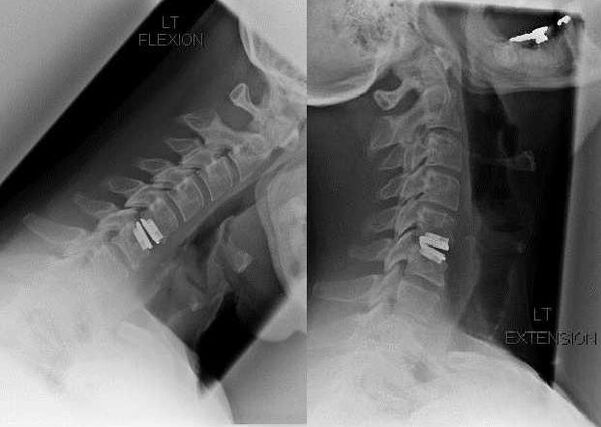

- Crunching, clicking when tilting or turning the head;

- limited mobility of the cervical spine;

- sharp, severe pain during exacerbations.

As the intervertebral discs and vertebrae deform, the patient's condition worsens.The course of osteochondrosis is complicated by neurogenic symptoms caused by compression by osteophytes or herniated protrusion of the spinal roots and vertebral artery.Headaches, dizziness, changes in blood pressure occur, and visual and hearing acuity decrease.